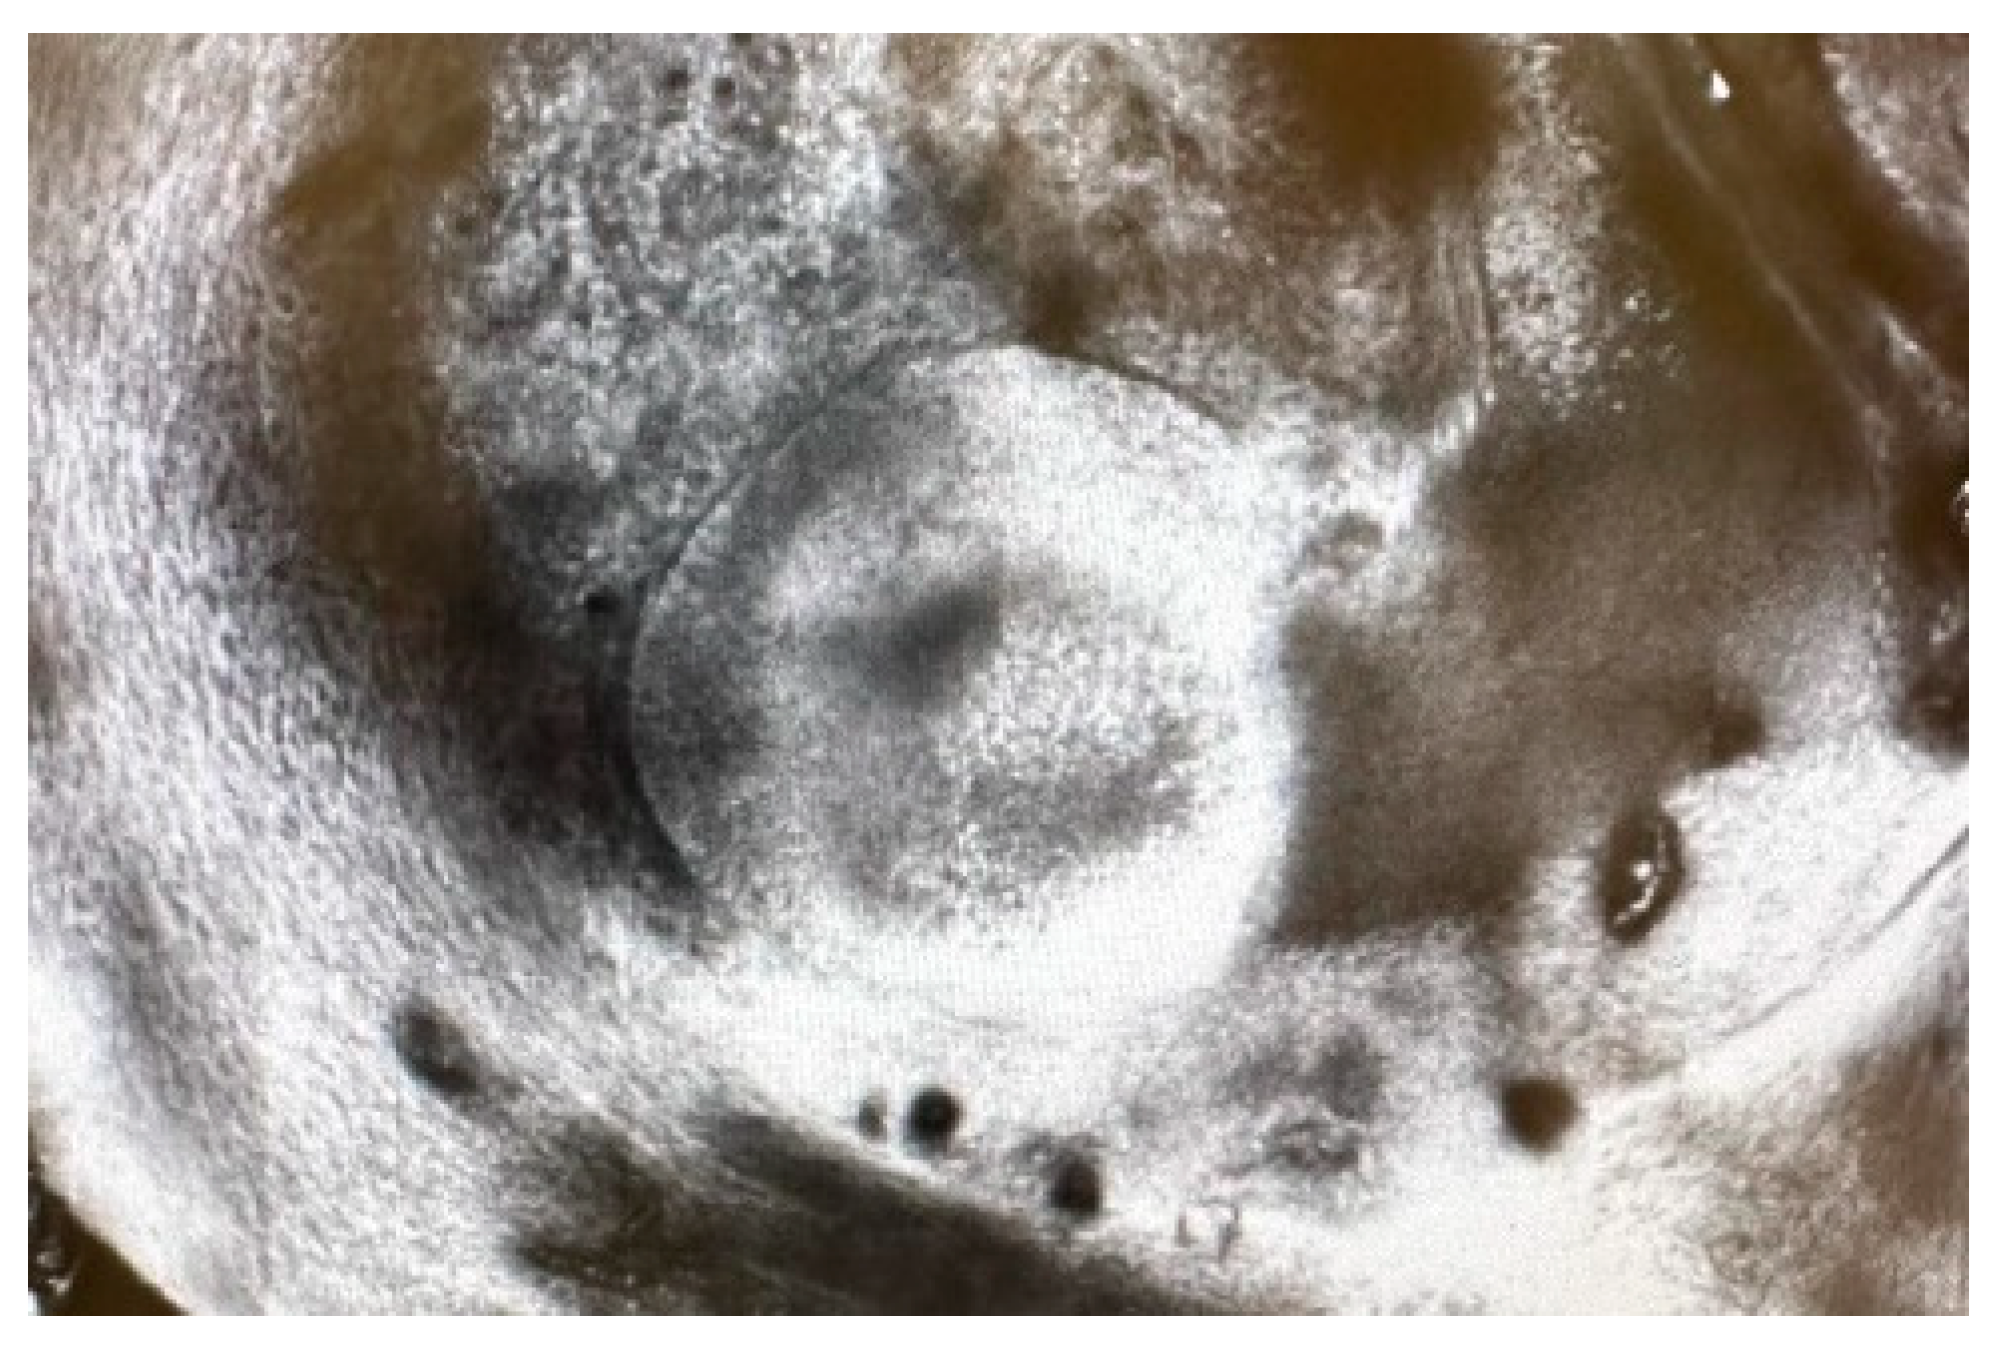

2. Case Report